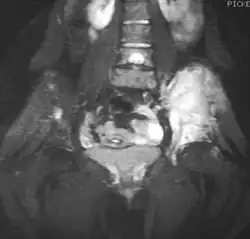

Magnetic resonance imaging (MRI) should be routinely used in the work-up of malignant tumors. It will show the full bony and soft tissue extent and relate the tumor to other nearby anatomic structures (e.g. vessels). Gadolinium contrast is not necessary as it does not give additional information over noncontrast studies, though some current researchers argue that dynamic, contrast-enhanced MRI may help determine the amount of necrosis within the tumor, thus help in determining response to treatment prior to surgery.[27]

Computed axial tomography (CT) can also be used to define the extraosseous extent of the tumor, especially in the skull, spine, ribs, and pelvis. Both CT and MRI can be used to follow response to radiation and/or chemotherapy. Bone scintigraphy can also be used to follow tumor response to therapy.[27]